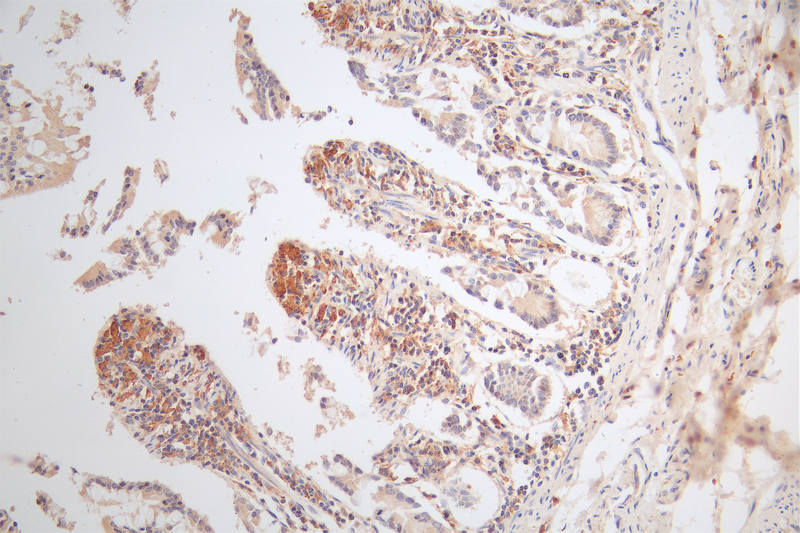

IHC image of CSB-RA574653A0HU diluted at 1:80 and staining in paraffin-embedded human small intestine tissue performed on a Leica BondTM system. After dewaxing and hydration, antigen retrieval was mediated by high pressure in a citrate buffer (pH 6.0). Section was blocked with 10% normal goat serum 30min at RT. Then primary antibody (1% BSA) was incubated at 4°C overnight. The primary is detected by a Goat anti-rabbit polymer IgG labeled by HRP and visualized using 0.49% DAB.